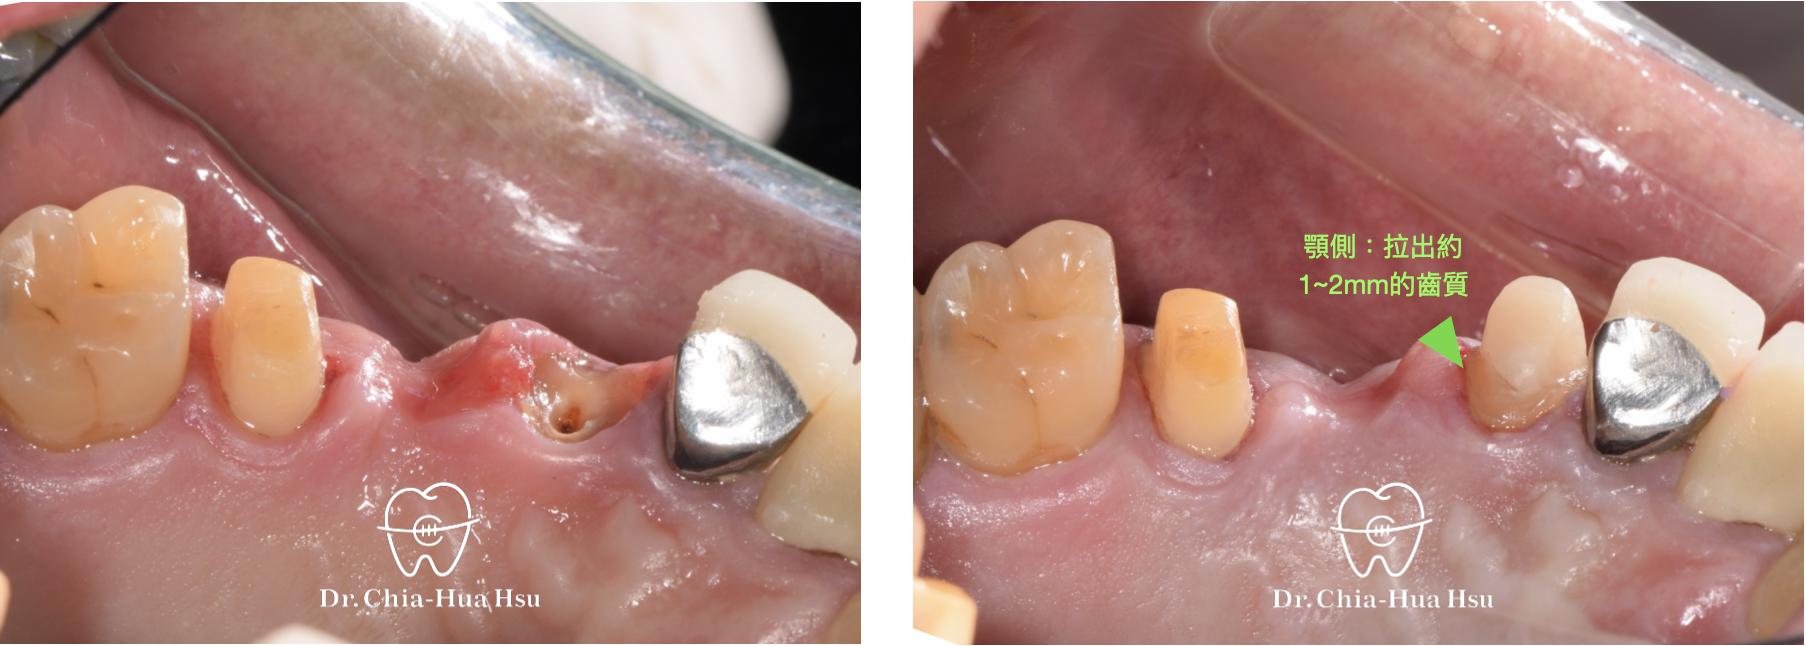

治療前

治療後

• 強逼萌出術 Forced eruption :在臨時牙橋上黏著金屬鈕扣,再使用橡皮圈把殘根牙齒拉出來以獲得足夠齒質(Ferrule effect),以利新的假牙製作。